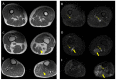

In the present study, through a case series, we highlighted the role of magnetic resonance (MR) in the identification and diagnosis of peripheral neuropathies. MR neurography allows the evaluation of the course of nerves through 2D and 3D STIR sequences with an isotropic voxel, whereas the relationship between nerves, vessels, osteo-ligamentous and muscular structures can be appraised with T1 sequences. Currently, DTI and tractography are mainly used for experimental purposes. MR neurography can be useful in detecting subtle nerve alterations, even before the onset of symptoms. However, despite being sensitive, MR neurography is not specific in detecting nerve injury and requires careful interpretation. For this reason, MR information should always be supported by instrumental clinical tests.